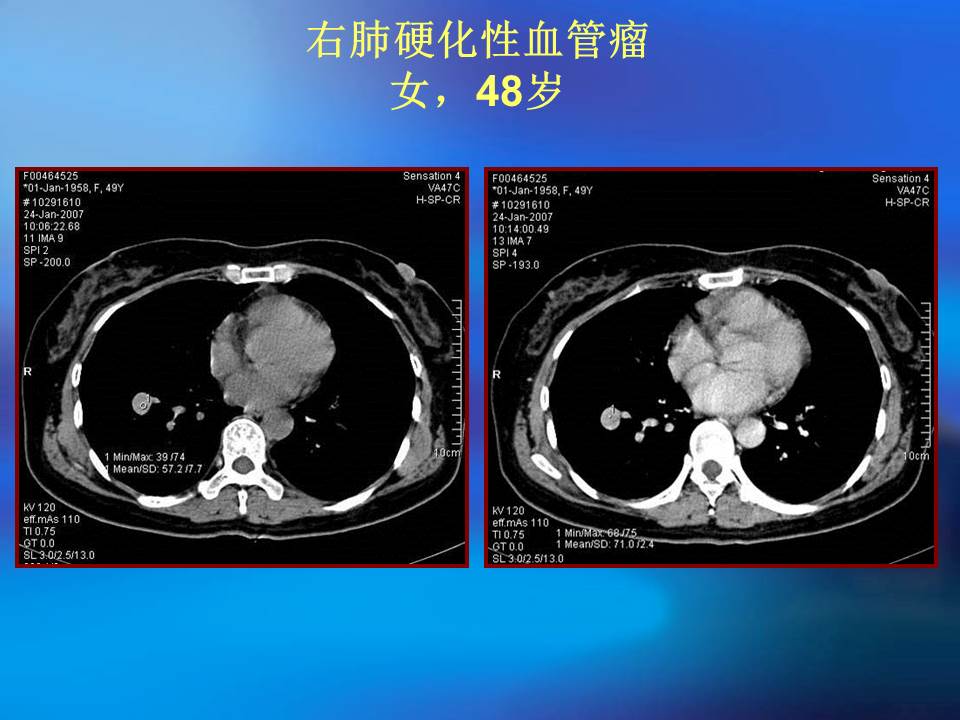

肺良性肿瘤